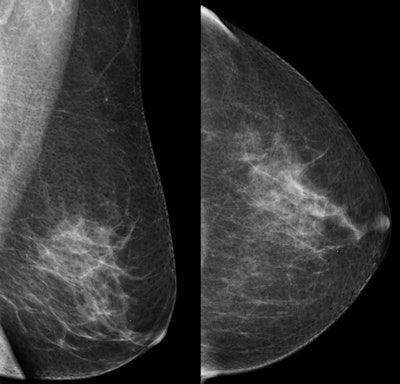

Top: Oblique and craniocaudal screening mammograms of a 51-year-old woman show no abnormality. Below: Ultrasound shows a 7-mm ductal invasive carcinoma (calipers). Bottom: Oblique and craniocaudal mammograms after ultrasound-guided core needle biopsy show clipmarker at biopsy site (arrow). All images courtesy of Dr. Wolfgang Buchberger.Data from past smaller studies on women with a higher risk of cancer show that adding handheld ultrasound to mammography for women with dense breasts increases cancer detection rates at the expense of lower specificity and lower positive predictive values, the authors noted (Eur J Radiol, April 2018, Vol. 101, pp. 24-29). Therefore, the team wanted to study how the addition of ultrasound, with its improved technology and reporting standards, could have an impact on mammography screening for a larger sample of women with an average breast cancer risk.